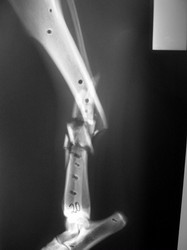

Fijación Externa

PRÁCTICAS CURSO DE FIJACIÓN EXTERNA PERFECCIONAMIENTO.

Híbrido.